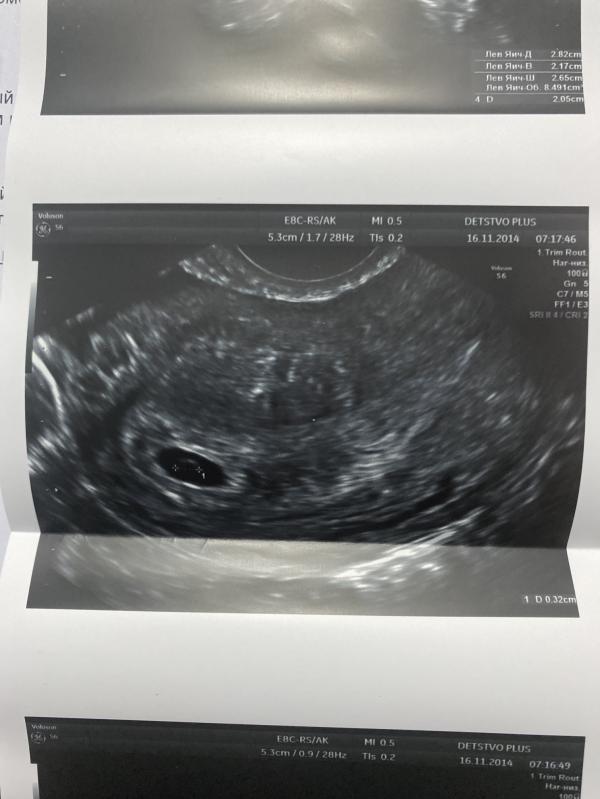

У меня сегодня увидели только ПЯ 9 мм, соответствие сроку( 3 недели и 1 день), желточный мешок 3 мм.